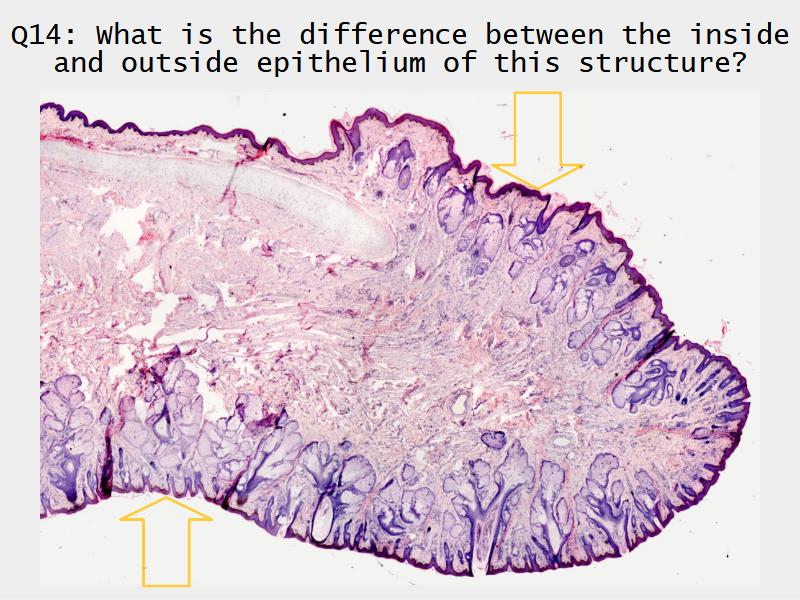

Slides: Respiratory System

- Slide 71: Nostril

Nostril